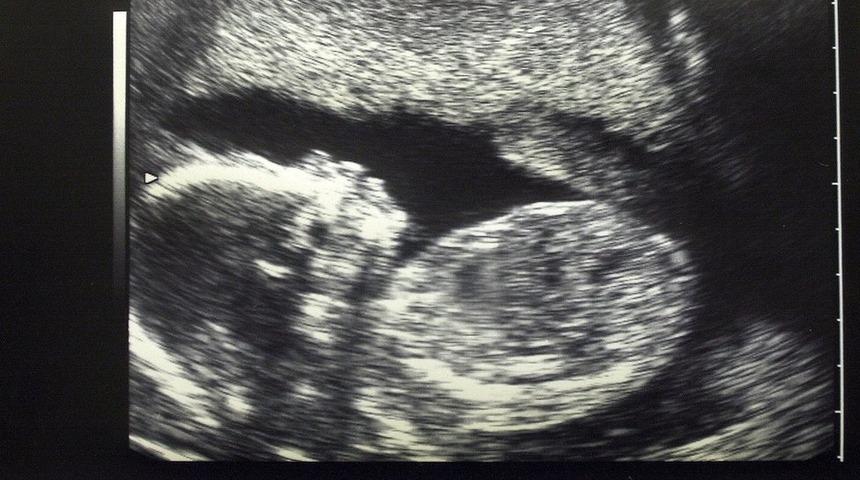

Hava kirliliği plasentaya kadar inerek 'doğmamış bebekleri de etkiliyor'

Belçika'da hamlie kadınlarla yapılan bir araştırmada plasentalarda hava kirliliği partikülleri bulundu. Uzmanlar, hamilelerin işlek caddelerden uzak durmasını tavsiye ediyor.

Belçika'da hamlie kadınlarla yapılan bir araştırmada plasentalarda (döleşi) hava kirliliği partikülleri bulundu.

Araştırma anne karnındaki bebeklerin de doğrudan trafik ve fosil yakıtların yakılmasından kaynaklanan kirliliğe maruz kaldıklarına işaret ediyor.